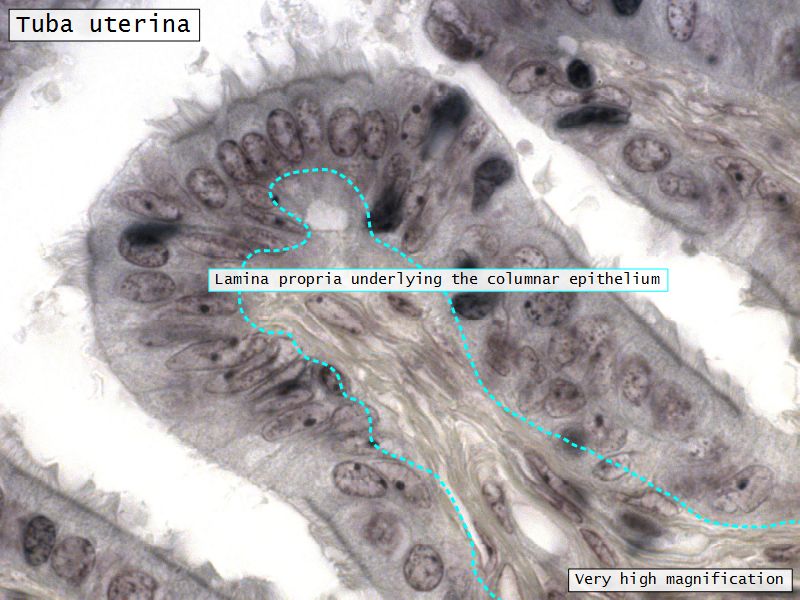

Mucosa

- Epithelium

- Lamina propria

Lamina propria

- Loose connective tissue

- Reticular fibres

- Fibroblasts

- Mast cells

- Lymphoid cells